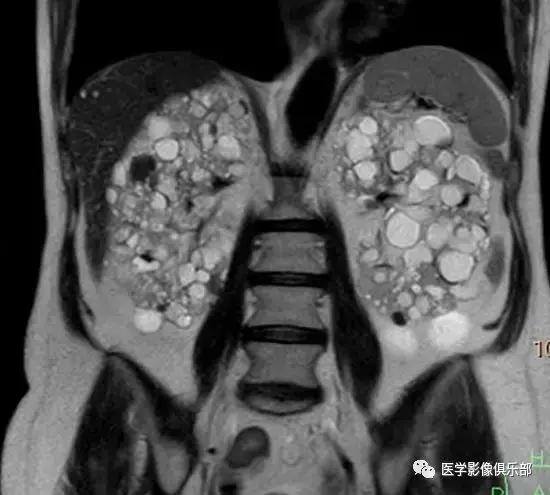

[典型病例二]:45岁,女性患者,腹部不适。家族史是动脉瘤性蛛网膜下腔出血和肾损害。

CTMPR冠状位重建显示双侧肾脏体积明显增大,肾脏皮质及髓质分界不清,弥漫大小不等的囊肿,边界光滑锐利,肝脏实质内亦可见多发大小不等的囊肿。